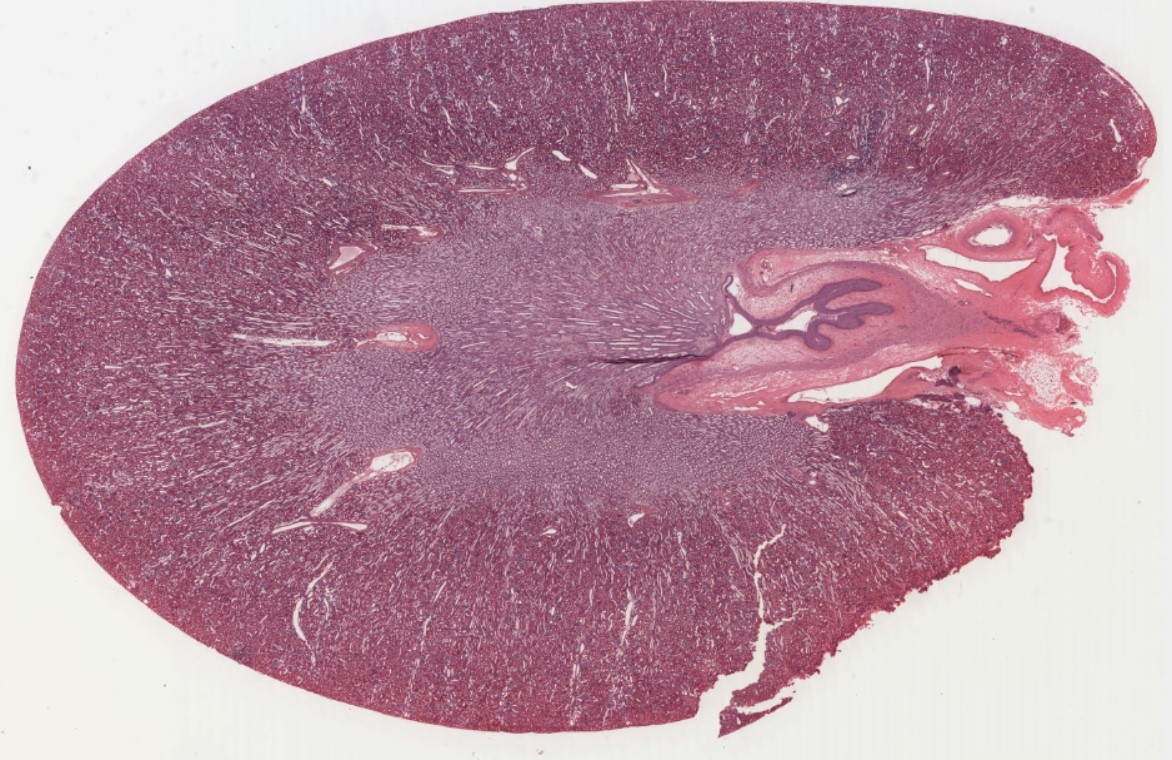

Image Link: https://histologyslides.med.umich.edu/Histology/Lymphatic%20System/026_HISTO_40X.htm